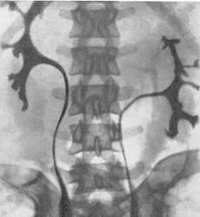

Торакальная дистопия диагностируется при проведении профилактической флюорографии или обзорной рентгенографии грудной клетки. Дистопированная почка чаще определяется как плотная округлая тень в заднем средостении над диафрагмой. Для правильной диагностики патологии и определения формы заболевания применяются визуализирующие урологические методы – УЗИ почек, ретроградная и экскреторная урография, радиоизотопная ренография (сцинтиграфия), почечная ангиография, МРТ, МСКТ почек.

УЗИ почек позволяет определить отсутствие почки на своем анатомическом месте и дифференцировать дистопию с нефроптозом. Экскреторная урография, как правило, точно выявляет аномальную локализацию почки, степень ее ротации и ограниченную подвижность. При резком снижении функции почек выполняется ретроградная пиелография. В ходе почечной ангиографии устанавливается уровень отхождения почечных артерий от ствола аорты. Дифференциальную диагностику аномалии проводят с нефроптозом, опухолями почки, кишечника, придатков.